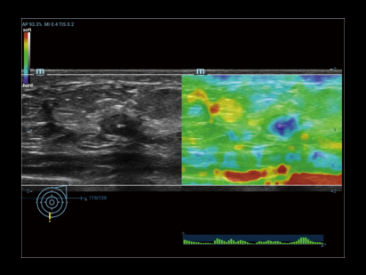

Kompleksowa elastografia odkszta?ceniowa i fali poprzecznej prostaty dla dw├│ch r├│?nych metod biopsji.

Elastografia prostaty: Nowotw├│r prostaty